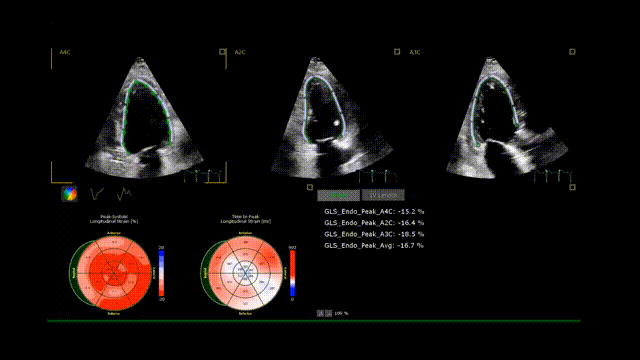

6、心尖四腔心切面: 评估左室射血分数(二维和/或三维)及左室整体纵向应变(global longitudinal strain,GLS)。需注意的是,评估左室整体纵向应变必须同时获得心尖四腔心、二腔心和三腔心视图(图7,视频4)。

图7. 左室整体纵向应变

利用四腔心切面(A)、二腔心切面(B)和三腔心切面(C)进行左室应变评估。这些图像经分析后,以靶心图形式(D)显示节段性纵向应变。

视频4. 利用四腔心、二腔心和三腔心切面获得左室整体纵向应变